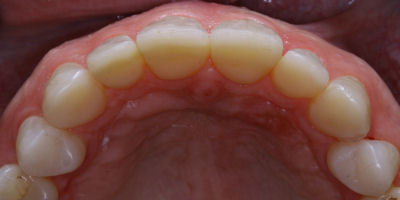

Closing Spaces